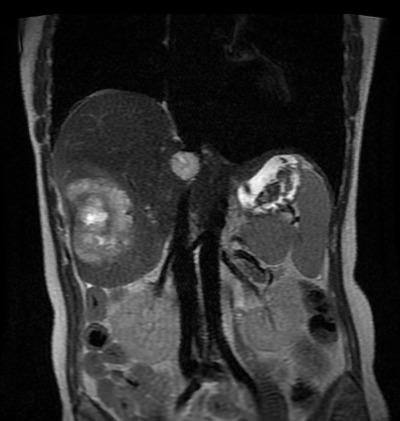

Métastases hépatiques (IRM)

2 masses hépatiques hétérogènes hypersignal T2.